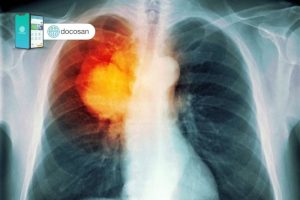

Ung thư phổi giai đoạn đầu làm sao nhận biết?

Ung thư phổi giai đoạn đầu cần được chẩn đoán, điều trị sớm thì kết quả điều trị sẽ tốt hơn, cải thiện tiên lượng sống còn của bệnh nhân. Tuy nhiên, bệnh nhân khi được chẩn đoán ung thư phổi đều đã ở giai đoạn muộn. Bài viết dưới đây của Doctor có sẵn […]